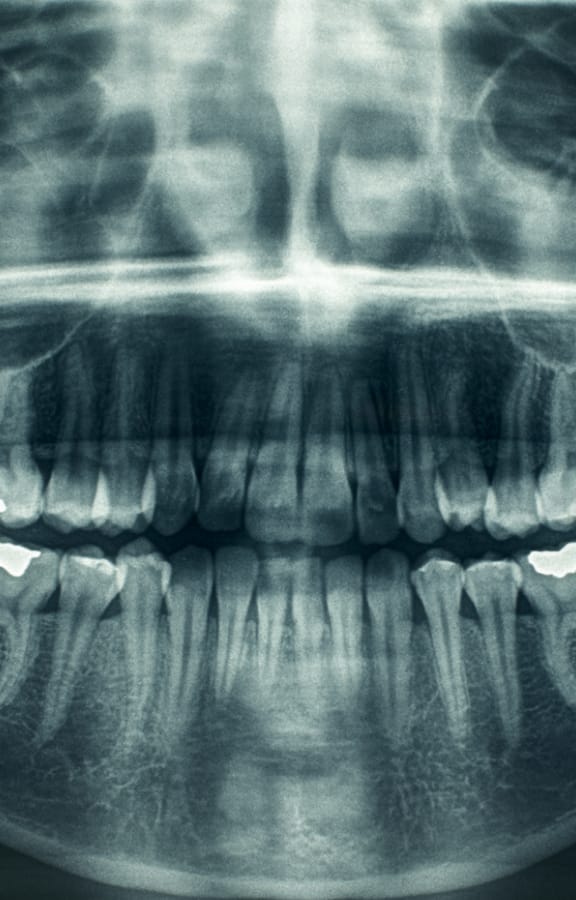

Bone grafting is commonly performed by an oral and maxillofacial surgeon to replace or augment bone in areas of tooth loss. Bone grafting to the jaws and facial structures may be necessary in a wide variety of scenarios. The most common bone grafts are facial skeleton and jaw procedures. Other common procedures include tooth extraction site graft, bone graft reconstruction and for a sinus lift. Shrinkage of bone often occurs when a tooth is lost due to trauma, severe caries, or periodontal disease. Additionally, bone loss may have already occurred due to infection or pathology around a tooth. There are many artificial biocompatible bone substitutes available; however, the best material for a bone graft is your own bone, which most likely will come from your chin, the back part of your lower jaw or your hip bone. The hip is considered to be a better source because the hip bone has a lot of marrow, which contains bone-forming cells. There are also synthetic materials that can be used for bone grafting. Most bone grafts use a person's own bone, possibly in combination with other materials.